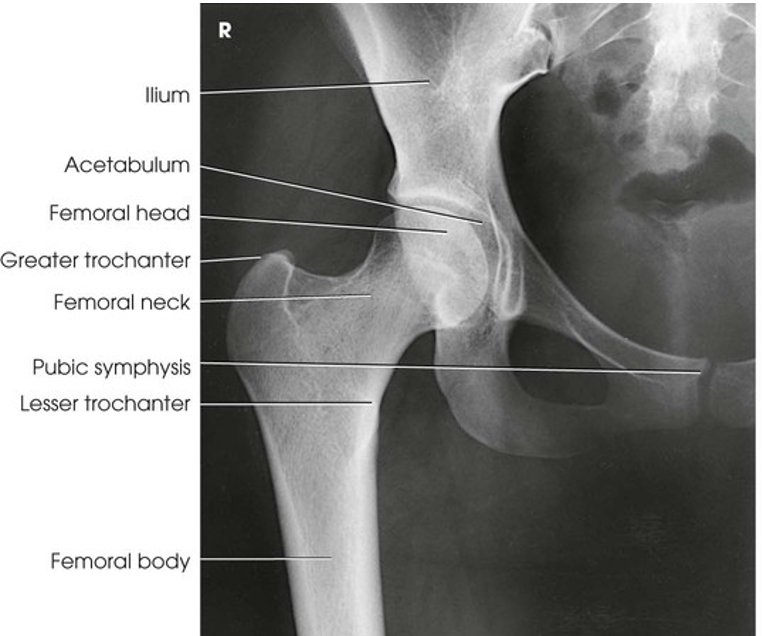

The image shows an AP projection of the pelvis and of the head, neck, trochanters, and proximal one third or one fourth of the shaft of the femora

AP Projection; Pelvis and Proximal Femora

AP Projection; Pelvis and Proximal Femora (Labeled)